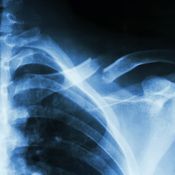

Ehdottomasti! Osteoporoosi antaa ensimerkkinsä usein vasta murtuman sattuessa. Kyse voi olla osteoporoottisesta murtumasta varsinkin silloin, jos kaatuminen kipeyttää lonkan, lantion, lannerangan, olan tai ranteen.

Osteoporoosi löytyy DXA-luuntiheysmittauksessa. Mittauksia tehdään myös yksityisesti, joten voit hakeutua sellaiseen varmuuden vuoksi.